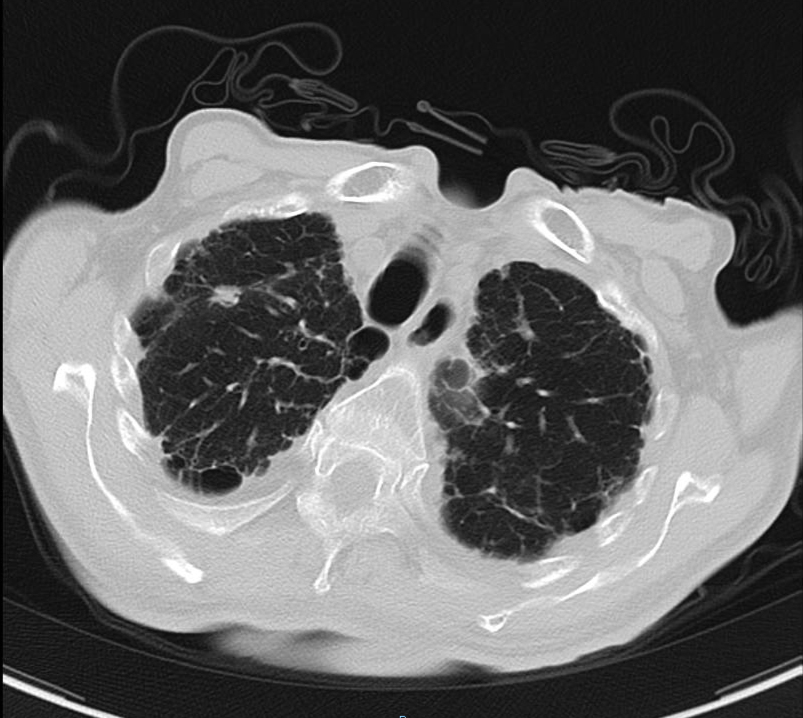

胸部CT回报:右肺间质性病变、双肺气肿、右上肺结节影、主动脉硬化、右侧胸膜钙化。

2020-01-08查胸部CT:双肺间质纤维化伴双肺气肿,双肺炎症,伴支气管扩张,右肺上叶结节样影,性质待定,双侧胸腔积液,纵膈多发肿大淋巴结,主动脉及冠状动脉硬化。

2020-08-31复查胸部CT:右肺结节影,结合病史考虑转移性病变,左侧局限性气胸,双肺气肿,双肺间质性病变,双侧胸腔积液;心脏增大,主动脉硬化。